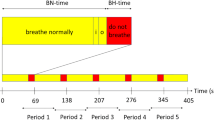

The breath-hold paradigm included 60 s of normal breathing, followed by 5 repetitive cycles, each involving 9 s end-expiratory breath-hold periods and 60 s of regular breathing. The breathing instructions were visually delivered via a wall-mounted display by use of a mirror affixed to the patient’s head coil. Presentation V20.1 (Neurobehavioral Systems, Berkeley, CA, USA) was applied to present the scanner triggered stimuli. Before the bh-fMRI examination, the breath-hold paradigm was explained to the patients, and the patients practiced the procedure outside the scanner.

Exemplary averaged bh-fMRI BOLD signal time-courses of each VOI of a one data set with steal phenomenon (visible in the territory of the left parietal MCA), b one data set with territorial time delay (visible in the territories of the right frontal and parietal MCA), and c one data set with neither steal phenomenon nor territorial time delay. The cerebellar signal time-courses are shown in red and the other VOIs’ signal time-courses in blue. Superimposed on each signal time-course is the mean cerebellar signal time-course in green. The duration of each averaged cycle was 69 s